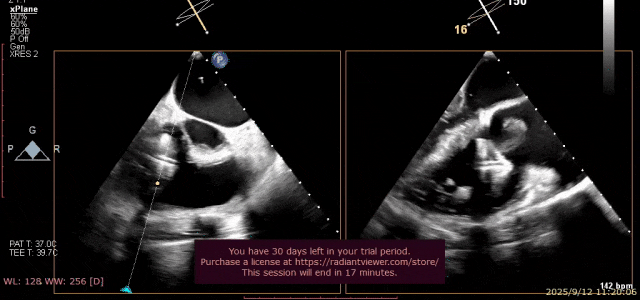

术前超声

图片

术前瓣叶